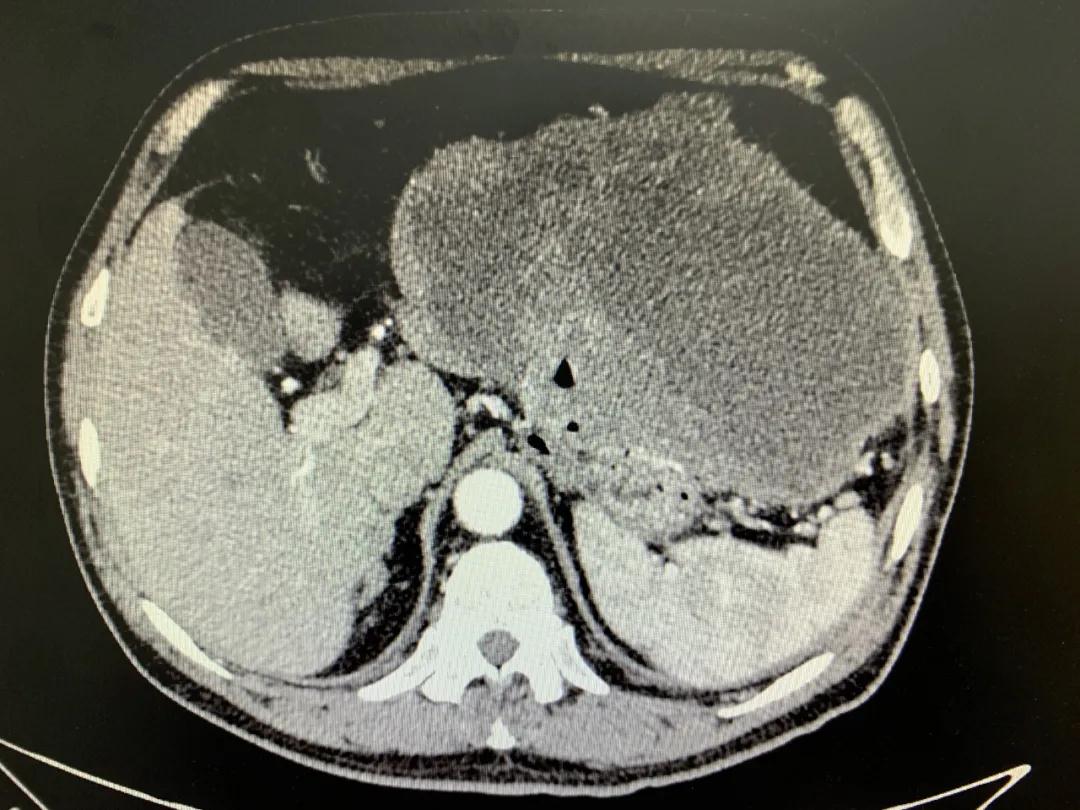

患者入院時血紅蛋白數(shù)值仍持續(xù)下降,出現(xiàn)失血性休克表現(xiàn),危及生命。消化外科二病區(qū)蔡磊主任接診后,組織科室迅速對患者進(jìn)行了全面的檢查。CT提示腫瘤大小約19.3*10.3cm,腫瘤內(nèi)提示大量積血。結(jié)合相關(guān)檢查,考慮為罕見的巨大胃間質(zhì)瘤合并出血。

蔡磊主任團(tuán)隊(duì)立即為患者安排了手術(shù),術(shù)中發(fā)現(xiàn)腫瘤巨大,占據(jù)大部分胃壁,胃腔內(nèi)殘存血液達(dá)3400ml之多,且多為新鮮活動性出血,給手術(shù)增加了非常大的難度。但蔡磊主任團(tuán)隊(duì)克服困難,在麻醉手術(shù)中心的幫助下,終于將腫瘤完整切除,術(shù)后稱量腫瘤達(dá)10斤重!